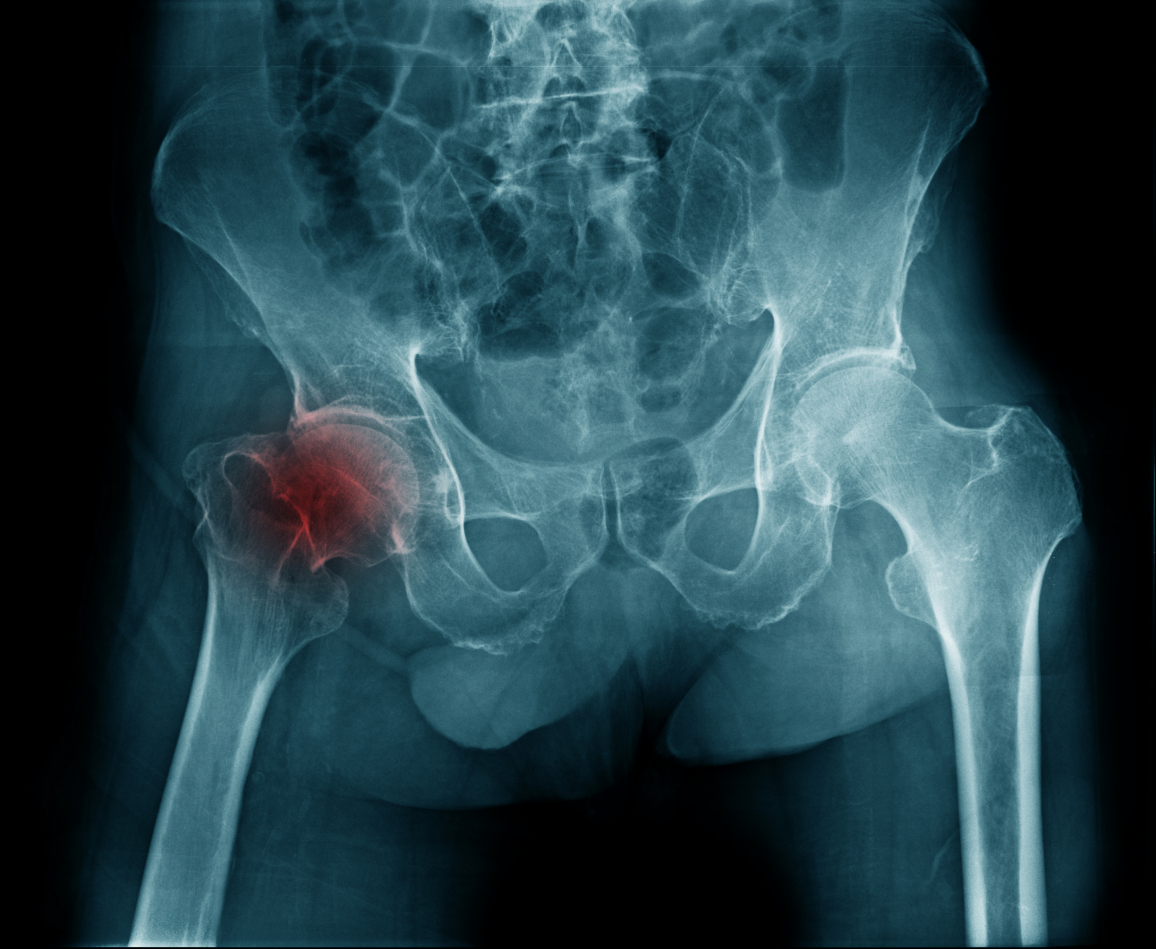

Диагностика перелома бедра

Для диагностики переломов бедра используется несколько методов:

- Рентгенография — основной метод визуализации для подтверждения и определения типа повреждения.

- КТ и МРТ — используются для уточнения диагноза, особенно при сложных повреждениях и повреждениях суставов.

- Компьютерная томография (КТ) — помогает оценить степень разрушения кости и повреждений мягких тканей.

- МРТ — необходим для оценки повреждений суставов, хрящей и связок.

Рентгенография является основным методом, однако при сомнительных случаях могут потребоваться дополнительные исследования, такие как КТ или МРТ.